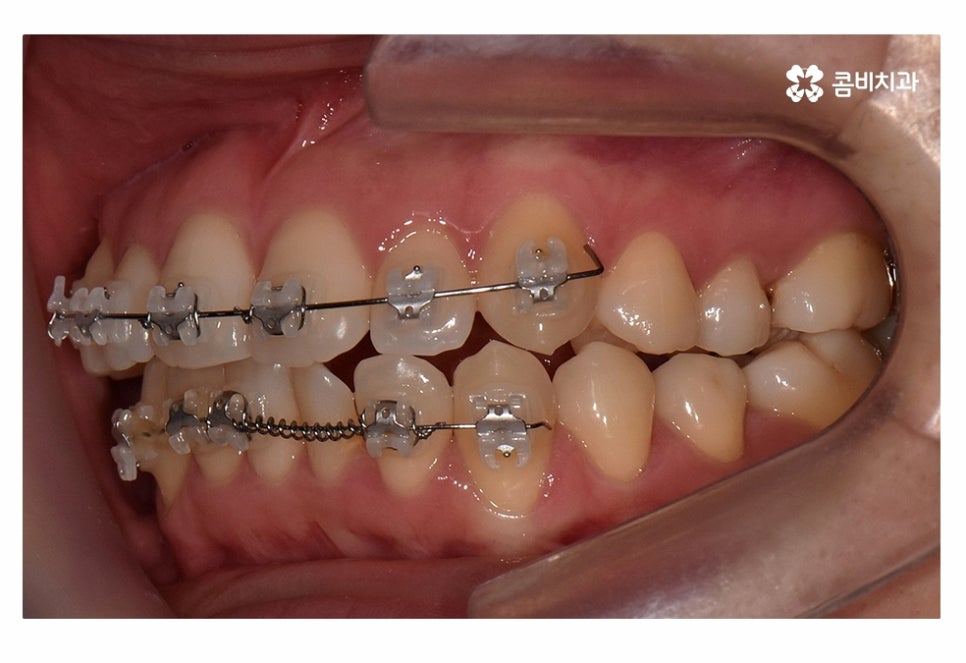

위 사진은 치료가 시작되고 약 5개월 정도가 지난 후의 모습인데

치아부분교정으로도 치열이 빠르게 가지런해진 모습을 볼 수 있어요.